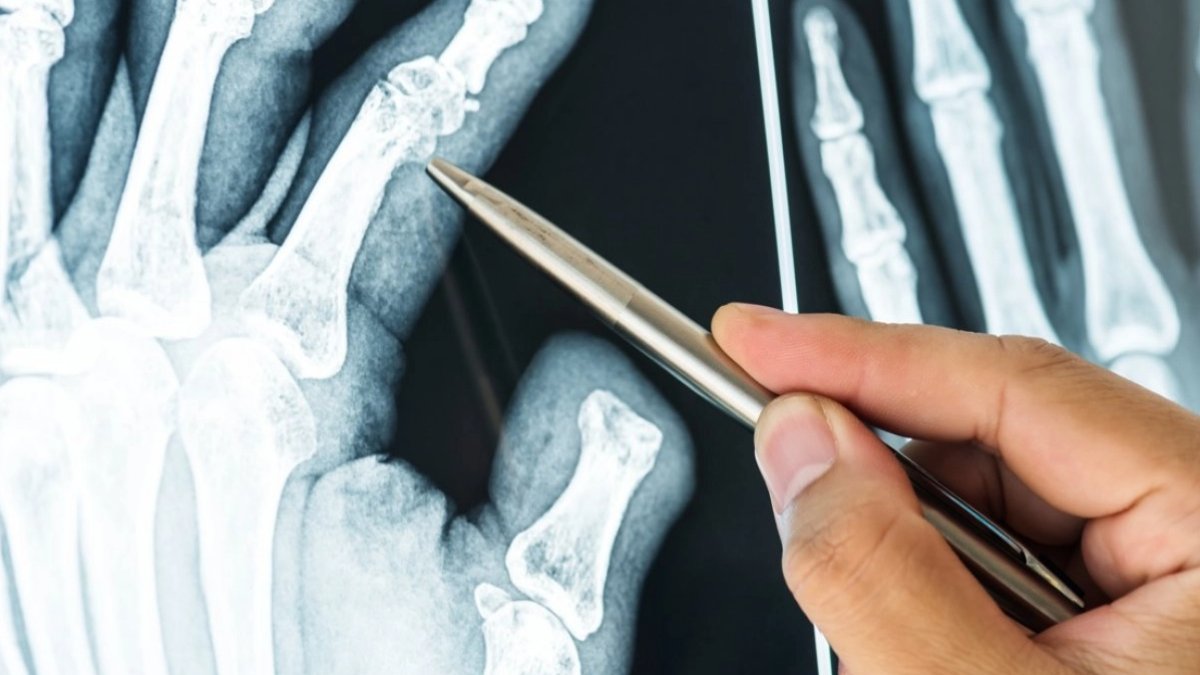

Kemik Kanseri Tanısı Nasıl Konur?

Kemik kanseri tanısı konulması için, doktorlar ayrıca kan testleri, biyopsi ve görüntüleme testleri de yapabilirler. Kan testleri, kanserin kemiklerin içine yayılıp yayılmadığını tespit etmek için yapılabilir. Biyopsi, kemik kanseri hücrelerinin mikroskop altında incelenmesi için alınan bir doku örneğidir. Görüntüleme testleri, kemik kanserinin yerini ve boyutunu belirlemeye yardımcı olabilir.